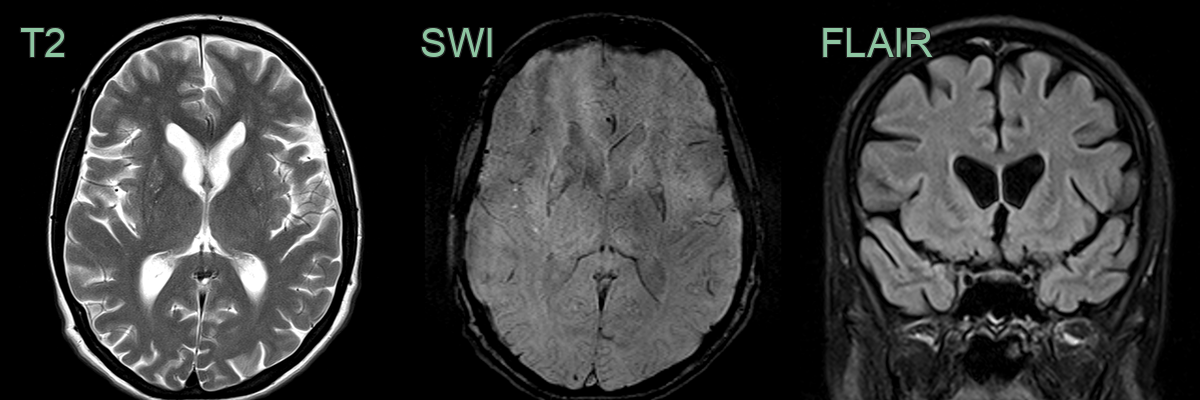

- 50-year-old male with increasing clumsiness and jerky arm movements.

- MRI showed atrophy and hyperintensity of the corpora striata on both sides.